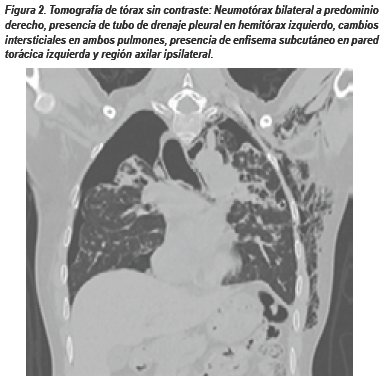

El manejo inicial consistió en colocación de drenaje pleural izquierdo a succión continua durante 15 días, al no evidenciar mejoría clínico radiológica, el paciente fue sometido a toracotomía exploradora izquierda. Durante el procedimiento se evidenció la presencia de bulas subpleurales múltiples, adherencias pleuromediastinales y del lóbulo inferior a diafragma, el parénquima pulmonar fue fibroso y se logró la expansión del lóbulo inferior, língula, el lóbulo superior expande parcialmente. Se realizó pleurodesis con talco hemostático y colocó drenaje pleural bilateral. En el postoperatorio el paciente tuvo manejo en unidad crítica por inestabilidad hemodinámica, fibrilación auricular e insuficiencia cardiaca, falleciendo 2 días después.